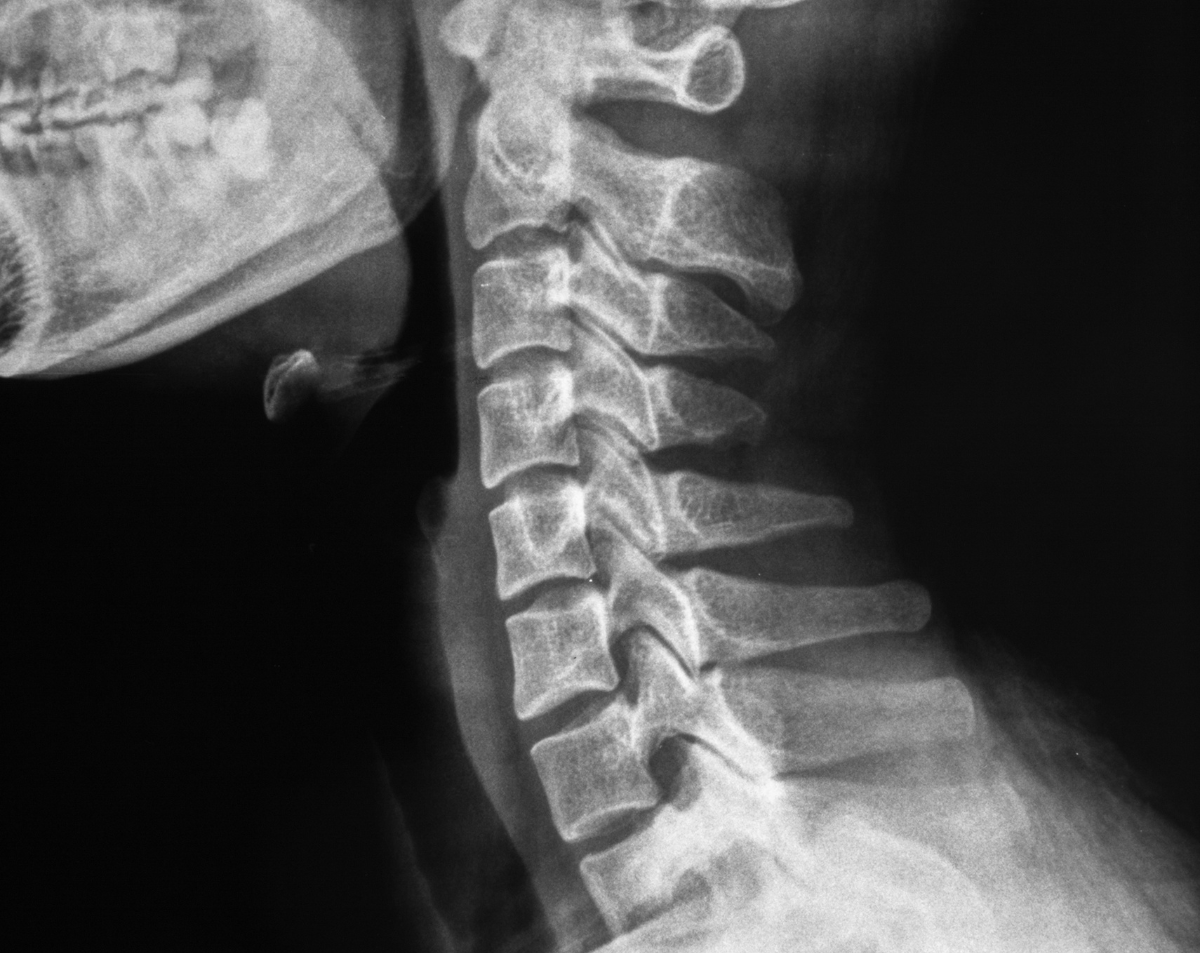

A cervical spine X-ray provides detailed images of the bones in the neck region of your spine. Physicians rely on this imaging test to evaluate trauma, chronic neck pain, degenerative changes, and alignment issues. At Desert Mobile Medical, we bring hospital-grade digital X-ray equipment directly to your doorstep. This means you receive expert diagnostics in the comfort and privacy of your home, office, or care facility—without long waits or crowded radiology centers.

Because it is fast and precise, a cervical spine X-ray is often the first diagnostic step before advanced scans such as MRI or CT.